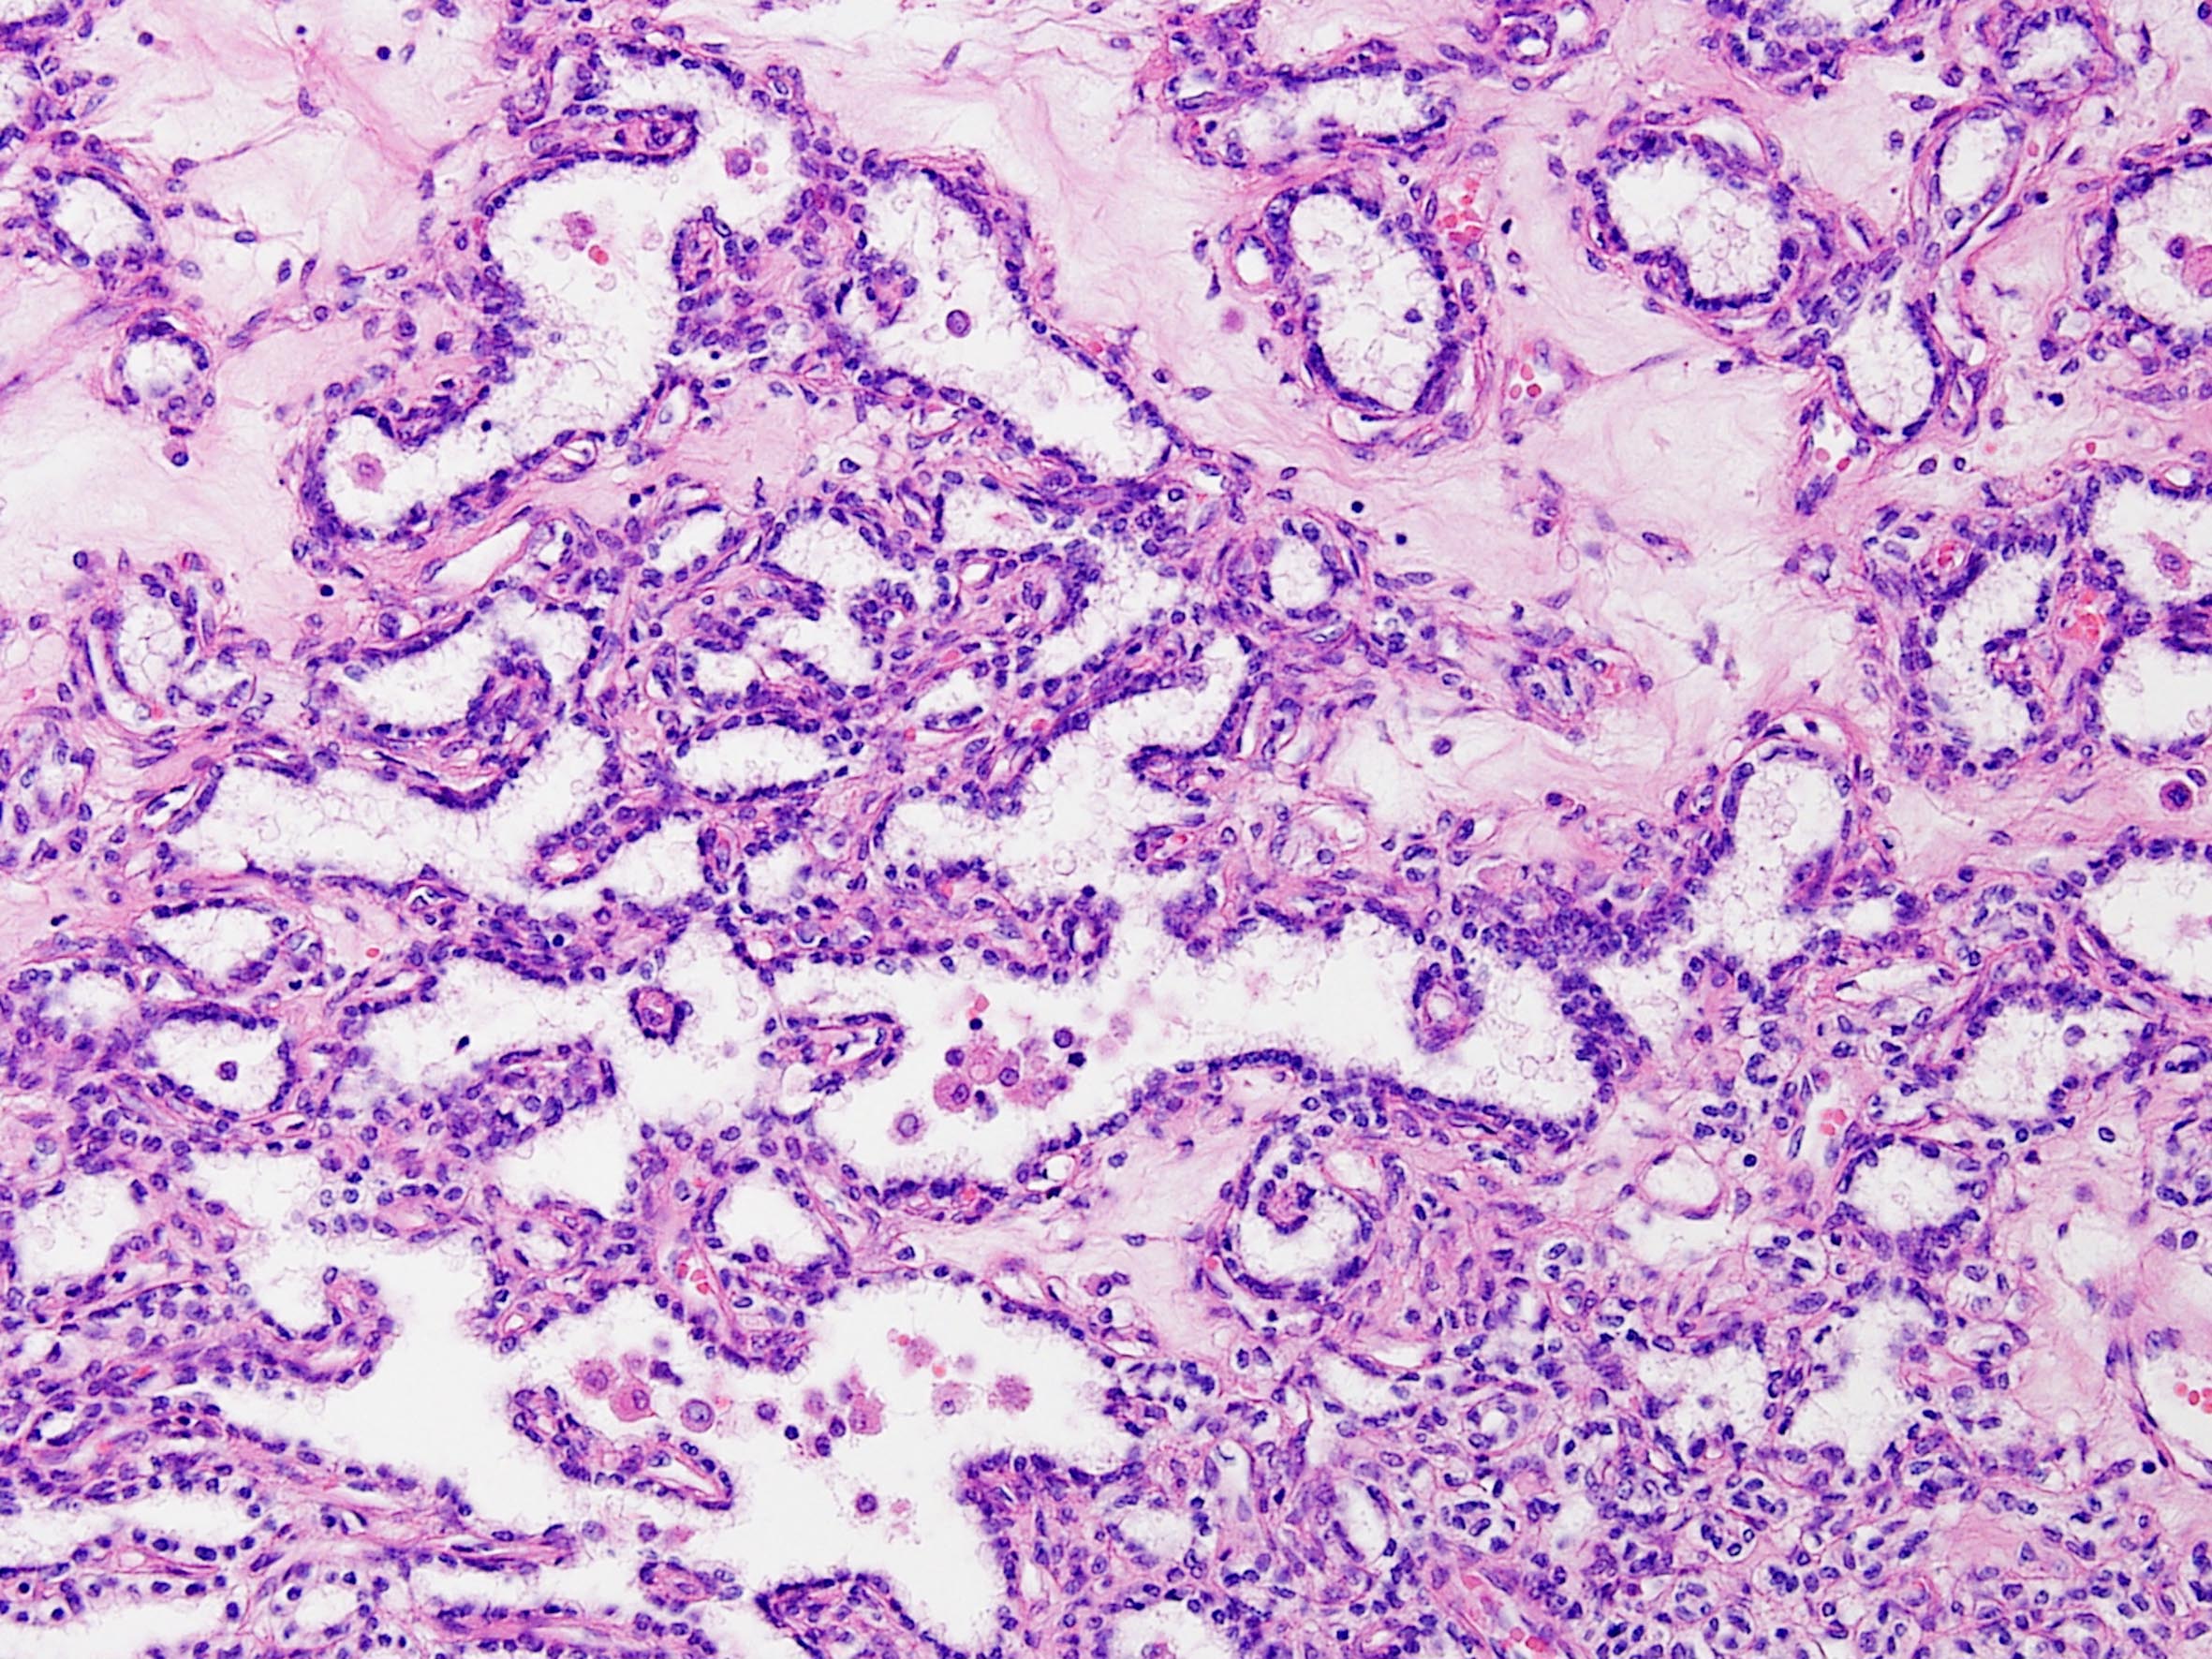

Classification of renal tumors

Case ID: 164